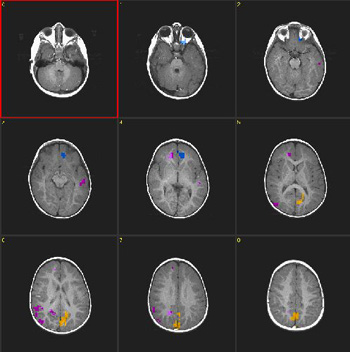

Case 3

| Patient | 4 year-old-boy with autism | ||||||

| Paradigm | ON: Presentation of flashing lights at 8 Hz, using special goggles OFF: Nothing. Patient sedated with nembutal | ||||||

| Statistics |

| ||||||

| Activation | Coronal cuts. The colored areas in the figure were obtained subtracting ON from OFF. Thus, the result shows "deactivation", which represent hyper extraction of oxygen occurring in the primary visual areas (V1). This finding is consistently found in young children either awake or under sedation. |